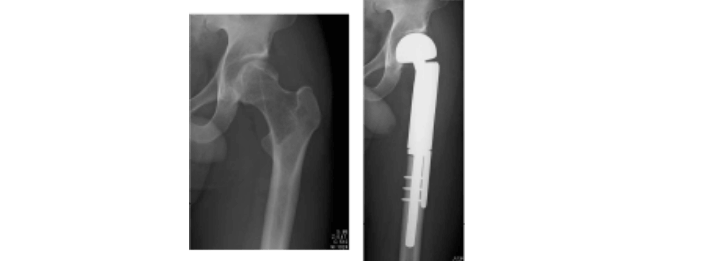

大腿骨頭壊死症

大腿骨頭の栄養血管である内側大腿回旋動脈の血流が障害され、大腿骨頭に骨壊死が生じる病態です。外傷など壊死の原因の明らかな症候性大腿骨頭壊死症とそうでない特発性大腿骨頭壊死症に分類されます。後者はステロイド薬による治療歴や習慣性飲酒のある患者に多いです。骨頭壊死の発生だけでは疼痛は出現せず、荷重により壊死骨が圧潰し、骨梁骨折や骨髄浮腫で発症します。大腿骨頭の圧潰は関節軟骨の障害を導き、変形性股関節症の変化を呈するようになります。荷重部においての壊死域の大きさは疾患の予後を決定する重要な因子で、単純X線像、MRIなどで評価されます。治療は、主に年齢、病期と壊死域によって決定され、骨切りや人工関節置換術などが行われます。

大腿骨頭回転骨切術・大腿骨彎曲内反骨切術

主に大腿骨頭壊死症に対して行う術式で、大腿骨頭に健常(正常骨)域が残っている場合は、大腿骨頭回転骨切り術や大腿骨弯曲内反骨切り術を行います。この手術は大腿骨の近位部で骨切りを行い、壊死していない正常な骨を荷重部に移動させる手術です。大腿骨頭の圧潰と関節症の進行を予防し、関節を温存することができます。